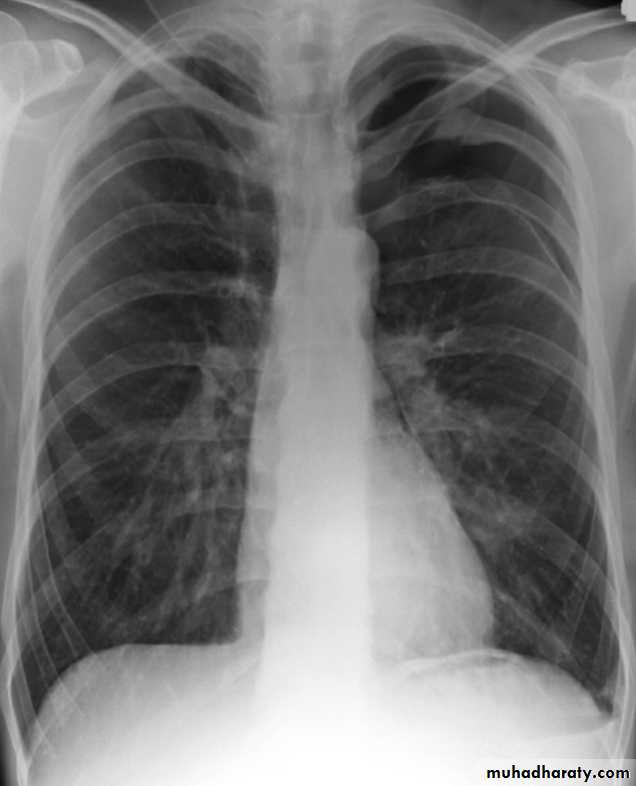

Pneumothorax

Pneumothorax refers to the presence of gas (air) in the pleural space. When this collection of gas is constantly enlarging with resulting compression of mediastinal structures it can be life-threatening and is known as a tension pneumothoraxIt is useful to divide pneumo thoraces into three categories :

Chest radiograph

A pneumothorax is, when looked for, usually relatively easily appreciated. Typically they demonstrate:

visible visceral pleural edge see as a very thin, sharp white line

no lung markings are seen peripheral to this line

the peripheral space is radiolucent compared to adjacent lung

the lung may completely collapse

the mediastinum should not shift away from the pneumothorax unless a tension pneumothorax is present